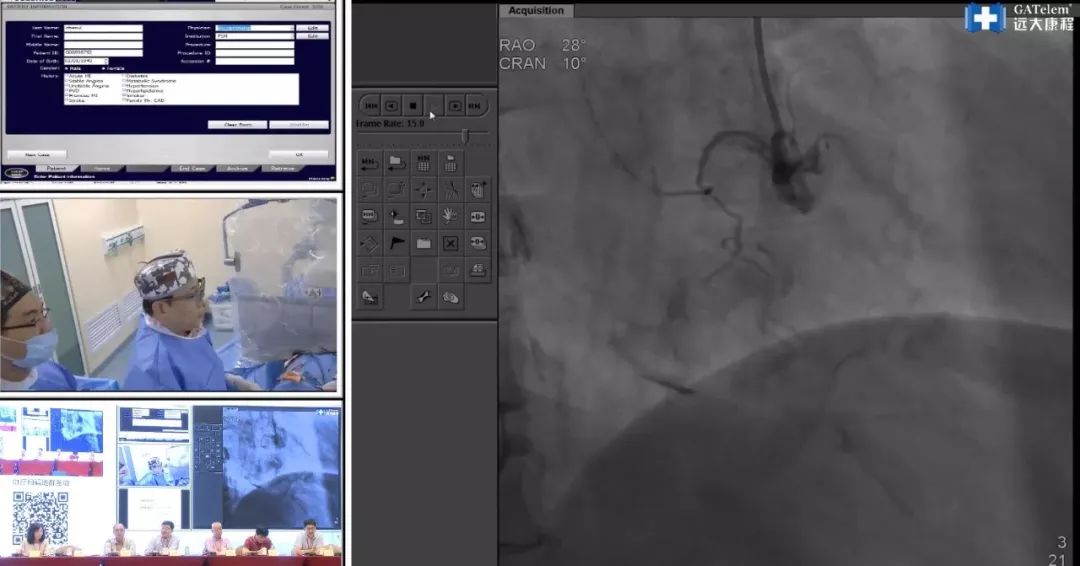

第一个病例由 南方医科大学南方医院修建成教授 进行手术演示,并由 空军军医大学西京医院李妍教授、中山大学附属第三医院陈林主任,北京安贞医院李宇教授,广州第一人民医院潘宜智教授,广西玉林市人民医院的李平教授 等共同主持讨论。

该病人为69岁的男性患者,既往有高血压病史。心脏造影显示该患者右冠状动脉存在齐头闭塞,且闭塞段较长,主要位于分叉之前的第二第三转折处。J-CTO评分为2分。右冠状动脉较大,存在侧支,回旋支细小,主要通过前降支向右冠状动脉供血。而其近端分支较大,但存在部分钙化,间隔支供血不充分。逆向来看,侧支丰富,然而远端血管迂曲,若发生并发症则患者将面临极大危险。但由于闭塞段较长,正向开通的可能性不大。

专家组认为,如何增强右冠状动脉的近端支撑力、指引导管的选择十分重要,但专家们分为两派各持己见。一方认为应该利用强支撑导管进行支撑,但另一方则持反对意见。他们担心强支撑导管会对右冠状动脉造成损伤。

术中,修教授选择了Amplatzer 1指引导管,然而前向开通CTO的过程中,遇到极大困难,存在较高风险,故尝试逆向开通策略。然而CT结果显示,右冠状动脉近端钙化,血管走形极为迂曲。第二段中部近90度夹角的存在增加了逆向导丝进入假腔的风险。术中,导丝在经过右始支的一个重度钙化狭窄时再次遇到了困难。

此例手术过程中,各位专家就指引导管的选择,导丝的选择,并发症的应对,逆向侧支的选择,如何个体化得进行正逆向的切换等问题进行了热烈的讨论,并纷纷表示各自获益匪浅。